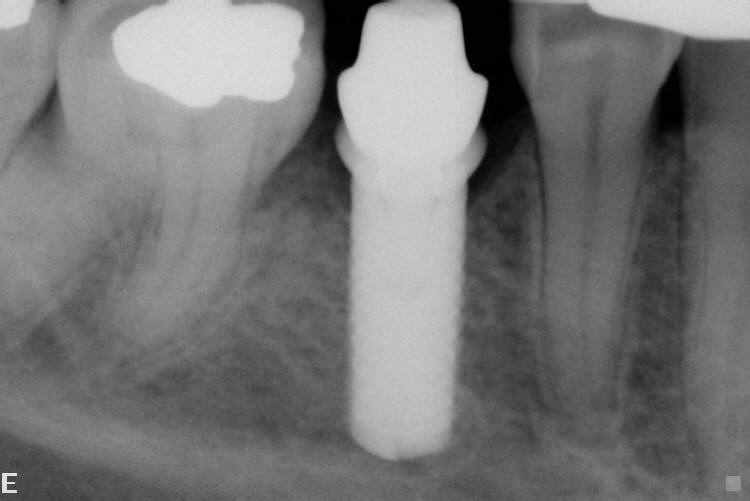

RX del posizionamento dell'impianto

RX controllo dell'impianto.